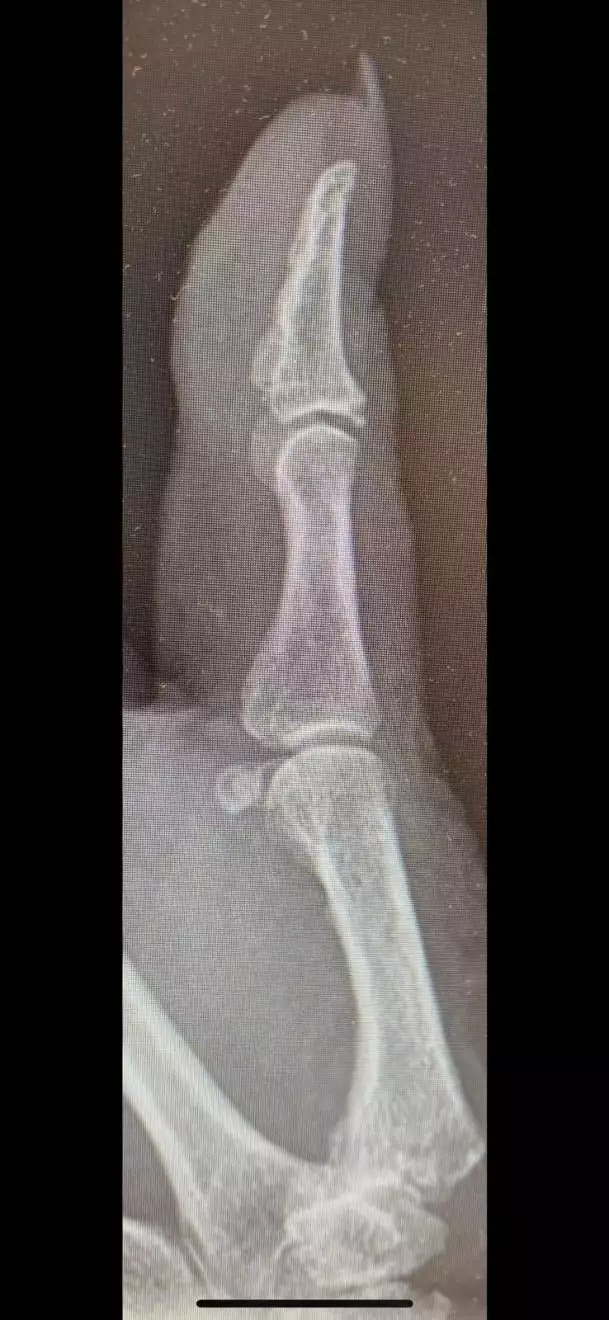

Die “TOUCH® DSG-Prothese” von Kerimedical ist eine Daumensattelgelenksprothese, die bei Arthrose des Daumensattelgelenks eingesetzt wird. Sie ist eine Weiterentwicklung der herkömmlichen Resektionsarthroplastik, bei der der Knochen (Trapezium) erhalten bleibt. Die Prothese zeichnet sich durch einen hochvernetzten Polyethylen-Einsatz aus, der eine hohe Verschleißfestigkeit aufweisen soll.

• Die Prothese besteht aus einem Metallteil, das am Mittelhandknochen befestigt wird, und einem hochvernetzten Polyethylen-Einsatz, der im Trapezium verbleibt.

• Sie ermöglicht eine Duo-Mobilität, also eine natürliche Bewegung des Daumens.